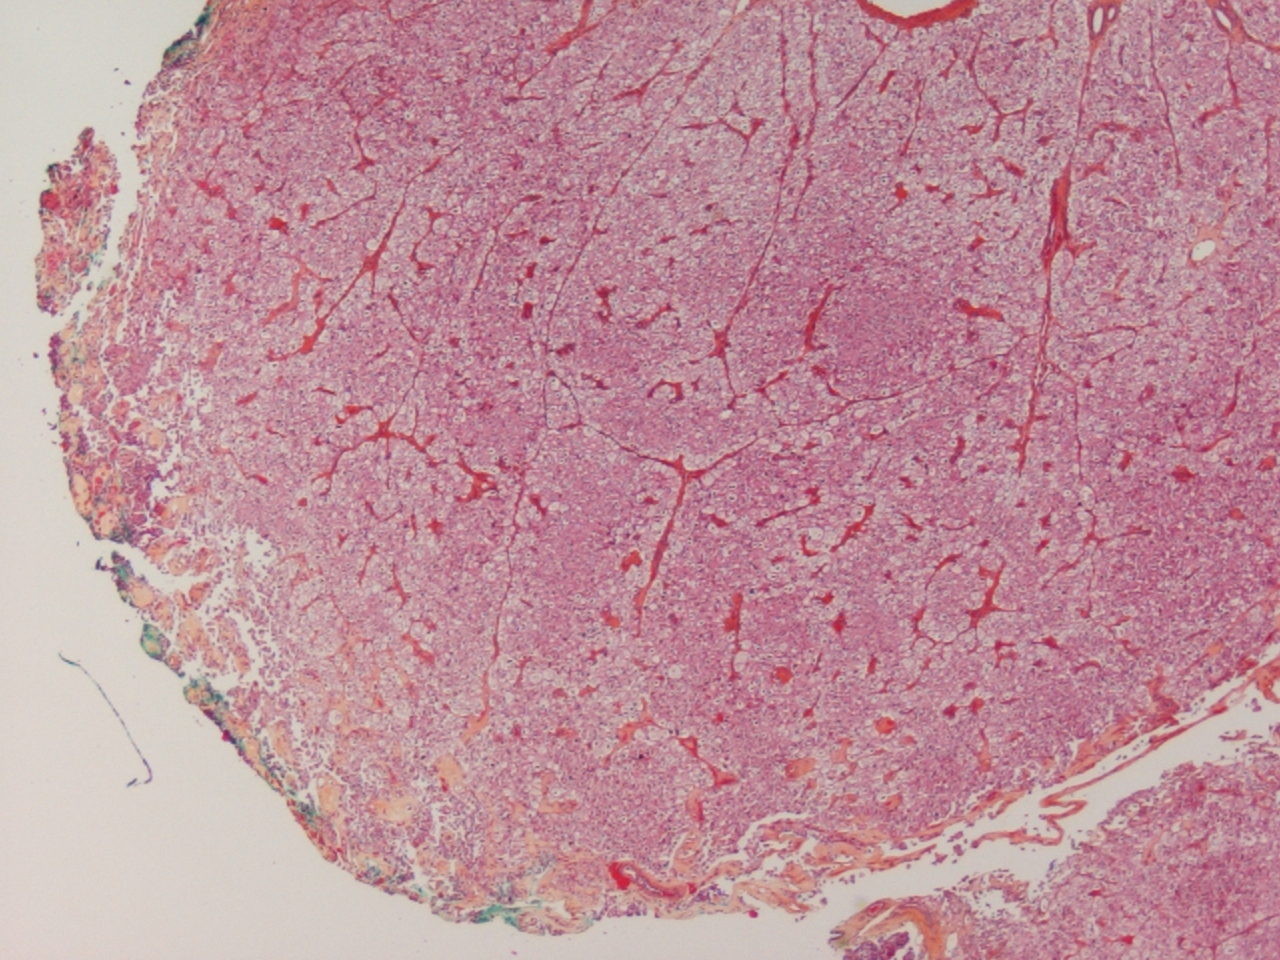

chromophobe RCC |

chromophobe |

just formal grading-I think it is chromophobe RCC |

chromophobe carcinoma